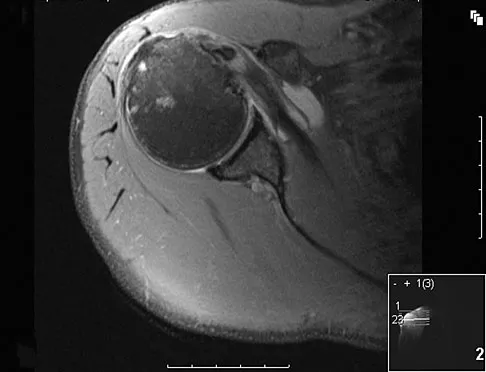

A 25-year-old tennis player has shoulder pain and weakness to external rotation. MRI scans are shown in Figures 16a and 16b. What is the most likely cause of his weakness?

Explanation